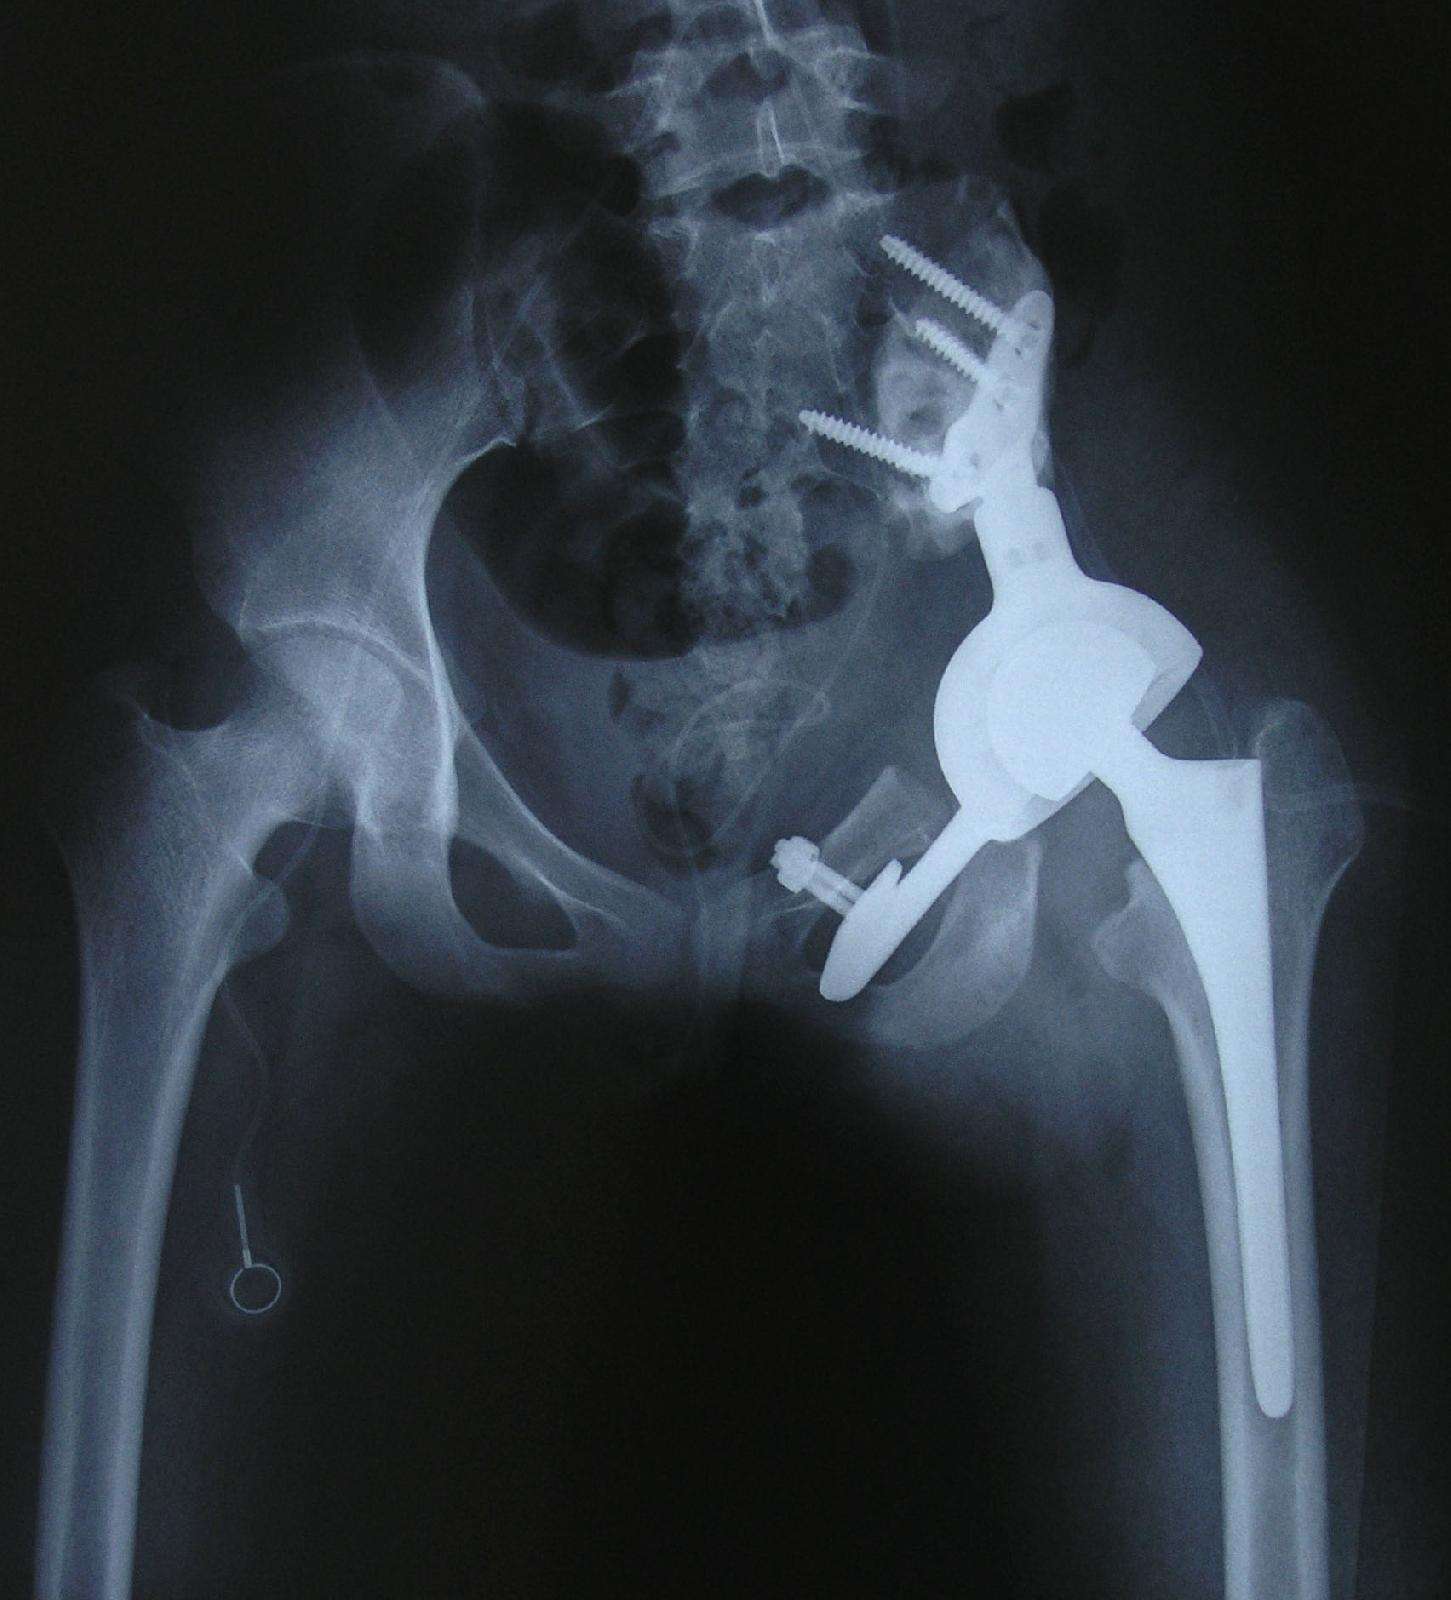

1、病例1:男 22岁 巨大骨盆骨肉瘤,大剂量化疗后行肿瘤广泛切除人工半骨盆假体置换术 。

术前X线片

术后X线片